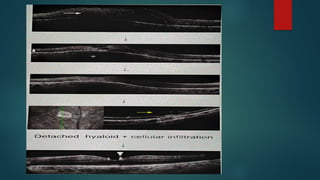

2. Inflammatory cellular infiltrate of

overlying vitreous:

 Granulomatous precipitates of

posterior hyaloid

 Dense vitreous opacities or

bands.

2. Inflammatory cellularinfiltrate of overlying vitreous:  Granulomatous precipitates of posterior hyaloid  Dense vitreous opacities or bands.  Active lesions can induce vitreous haze causing HEADLIGHT IN FOG APPEARANCE